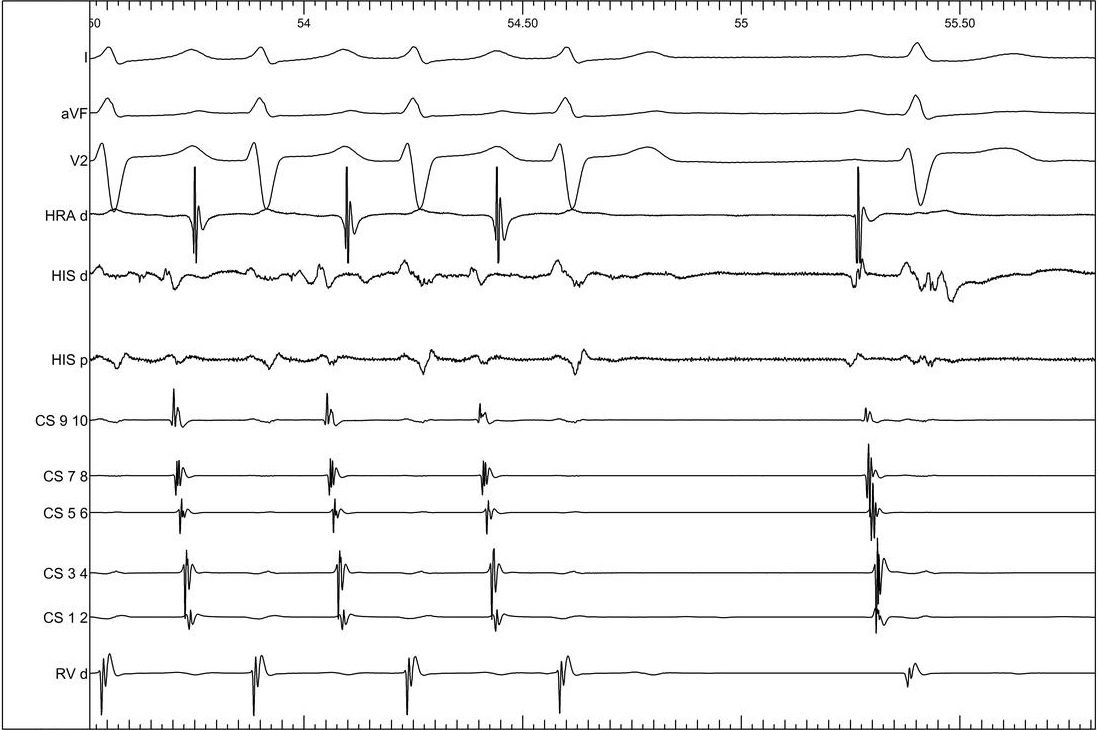

Incremental ventricular pacing

01_vawb.jpg